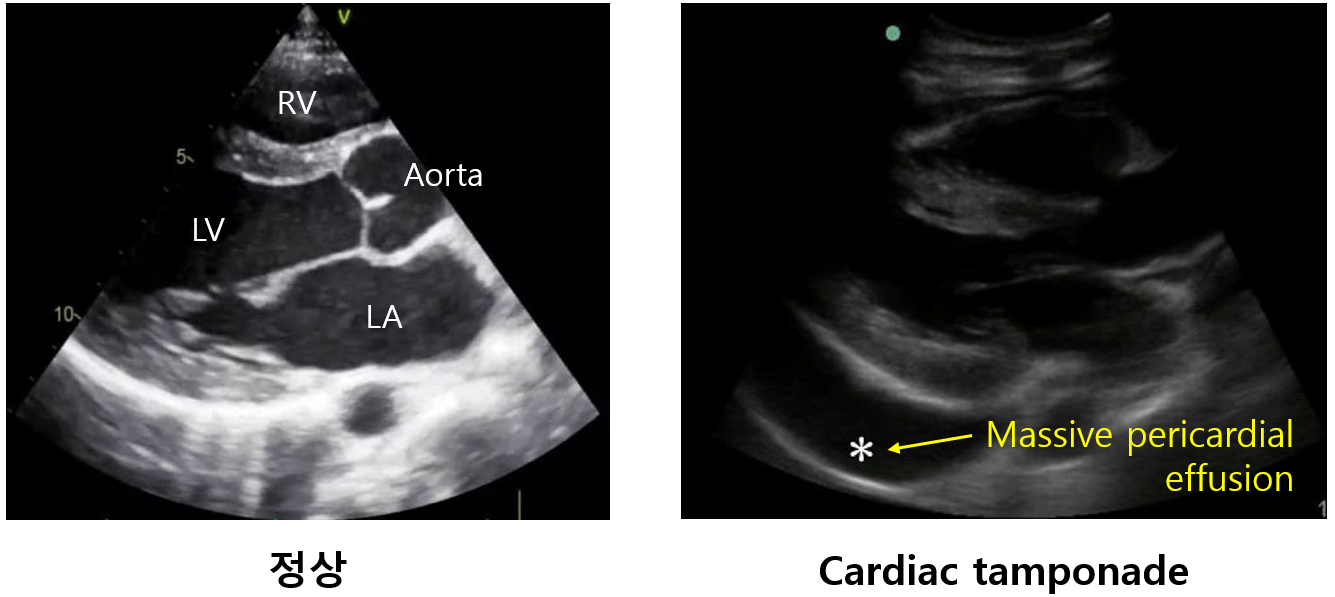

1) 경흉부심초음파(echocardiography): 1st line

(1) Massive pericardial effusion: 보통 > 1~2 cm

(2) Systole 때 RA collapse, diastole 때 RV collapse

* 원래 systole 때 RA가 충만하고, diastole 때 RV가 충만해야 한다. 하지만 pericardial effusion으로 인해 filling이 방해를 받아 오히려 각자 충만해야 할 시기에 collapse되는 것이다. LV에 비해 RV의 myocardium이 얇고 약하므로 effusion에 의한 외력에 더 취약하다.